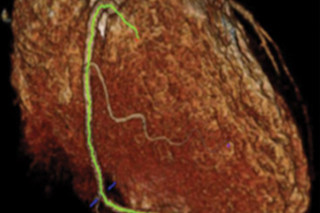

Mapping fat accumulation around arteries in the heart. (Credit: A.S. Antonopoulos et al., Science Translational Medicine (2017)) A new, noninvasive imaging method lets researchers pick up on the warning signs of heart disease long before a heart attack or stroke can take place. The noninvasive technique uses current computed tomography (CT) scanning technology to analyze images of fatty deposits lining blood vessels in order to flag potentially dangerous inflammation. Using the data from heart scans, researchers from the University of Oxford developed an index measuring changes in fat tissues around blood vessels to determine if patients are at risk of developing heart disease.

The method developed at Oxford does just that. One key observation drove the breakthrough: The fat surrounding arteries begin to look different when they become inflamed, which is a precursor of more serious damage. Inflammatory proteins called cytokines prevent the tissues from holding on to lipids, resulting in more watery-looking fat deposits. With the CT scans, the researchers can watch this process occur and pinpoint areas prone to plaque build-up. In addition, they say that their technique can also identify plaques that are in danger of bursting free from artery walls and stopping blood flow to the heart or brain. After initial tests on tissues donated by patients undergoing heart surgery, they compared their CT-scan prognosis to measurements of inflammation taken by positron emission tomography (PET). The results match up, they say, indicating that the much less expensive CT scans can perform the same function. They also applied the technique to 273 patients, some of whom had heart disease and some who didn't, to see if they could predict health outcomes for them. Among the five who had heart attacks, they saw the kind of changes in fat tissues that heralded heart disease. The results were published today in Science Translational Medicine. While the technique uses equipment already common in hospitals, it does require special software, the researchers say. They hope to develop user-friendly versions of the program, but for the moment, the technique can only be used at their lab in Oxford. As they continue to develop the process it should also be useful in detecting other medical emergencies like strokes and aortic aneurysms. Underway at the moment is a large-scale clinical trial of their technique, they say, the results of which should be published before the end of the year.